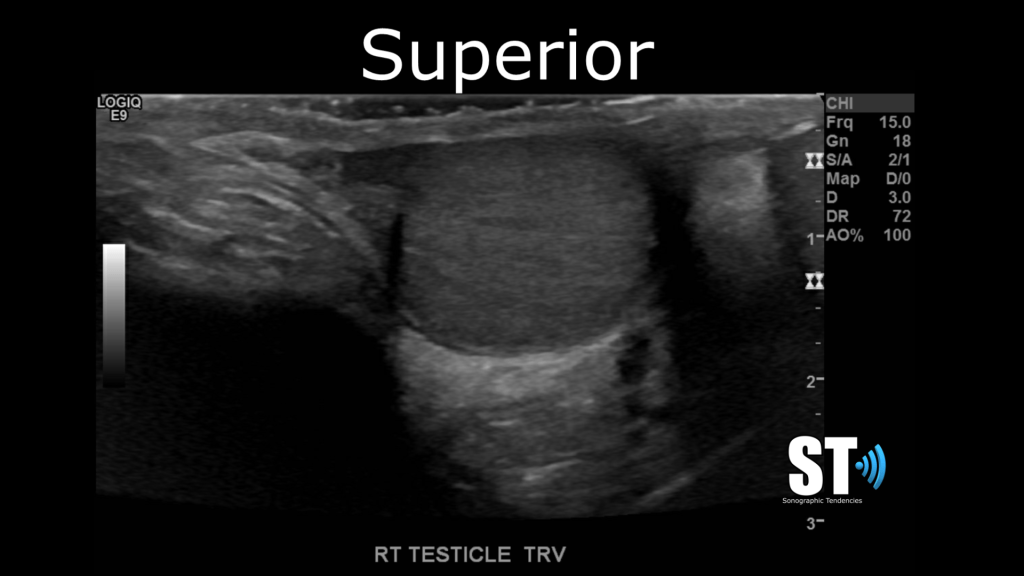

Transverse

In transvers beginning at the superior pole take images of starting at the epididymal head and capture images of the superior, mid section and inferior poles of the testis.